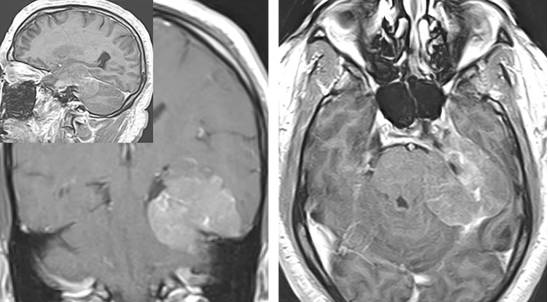

磁共振可以清楚地显示肿瘤的大小、形状、幕上下的累及范围、天幕的肿瘤基底范围以及与周围神经和血管组织的关系。T2序列上的血管流空影可以显示出肿瘤与后循环动脉的关系。

脑实质水肿高度提示肿瘤已经突破软脑膜,磁共振的动脉和静脉显影会显示出血管的分布和走行。磁共振静脉显影可以显示出Galen静脉、直窦和相关的基底静脉。横窦和乙状窦的走行及与肿瘤的关系对于“外环”区域肿瘤非常重要。已经被肿瘤完全侵蚀的静脉窦腔由于无血流通过可以直接切除而不会造成大量出血,但若静脉窦腔尚未被肿瘤完全侵蚀,则只能保留静脉窦而对肿瘤进行部分切除。

图1. 图示天幕脑膜瘤。术者通过经天幕小脑上入路来避免术中由于暴露不够而对颞叶的切除。

图2. 天幕脑膜瘤。如上图所示病例,肿瘤可以沿天幕表面扩展。在此患者中,后颅窝的占位压迫导致相应症状。此病例分期分别通过乳突后和颞下入路两步来切除。